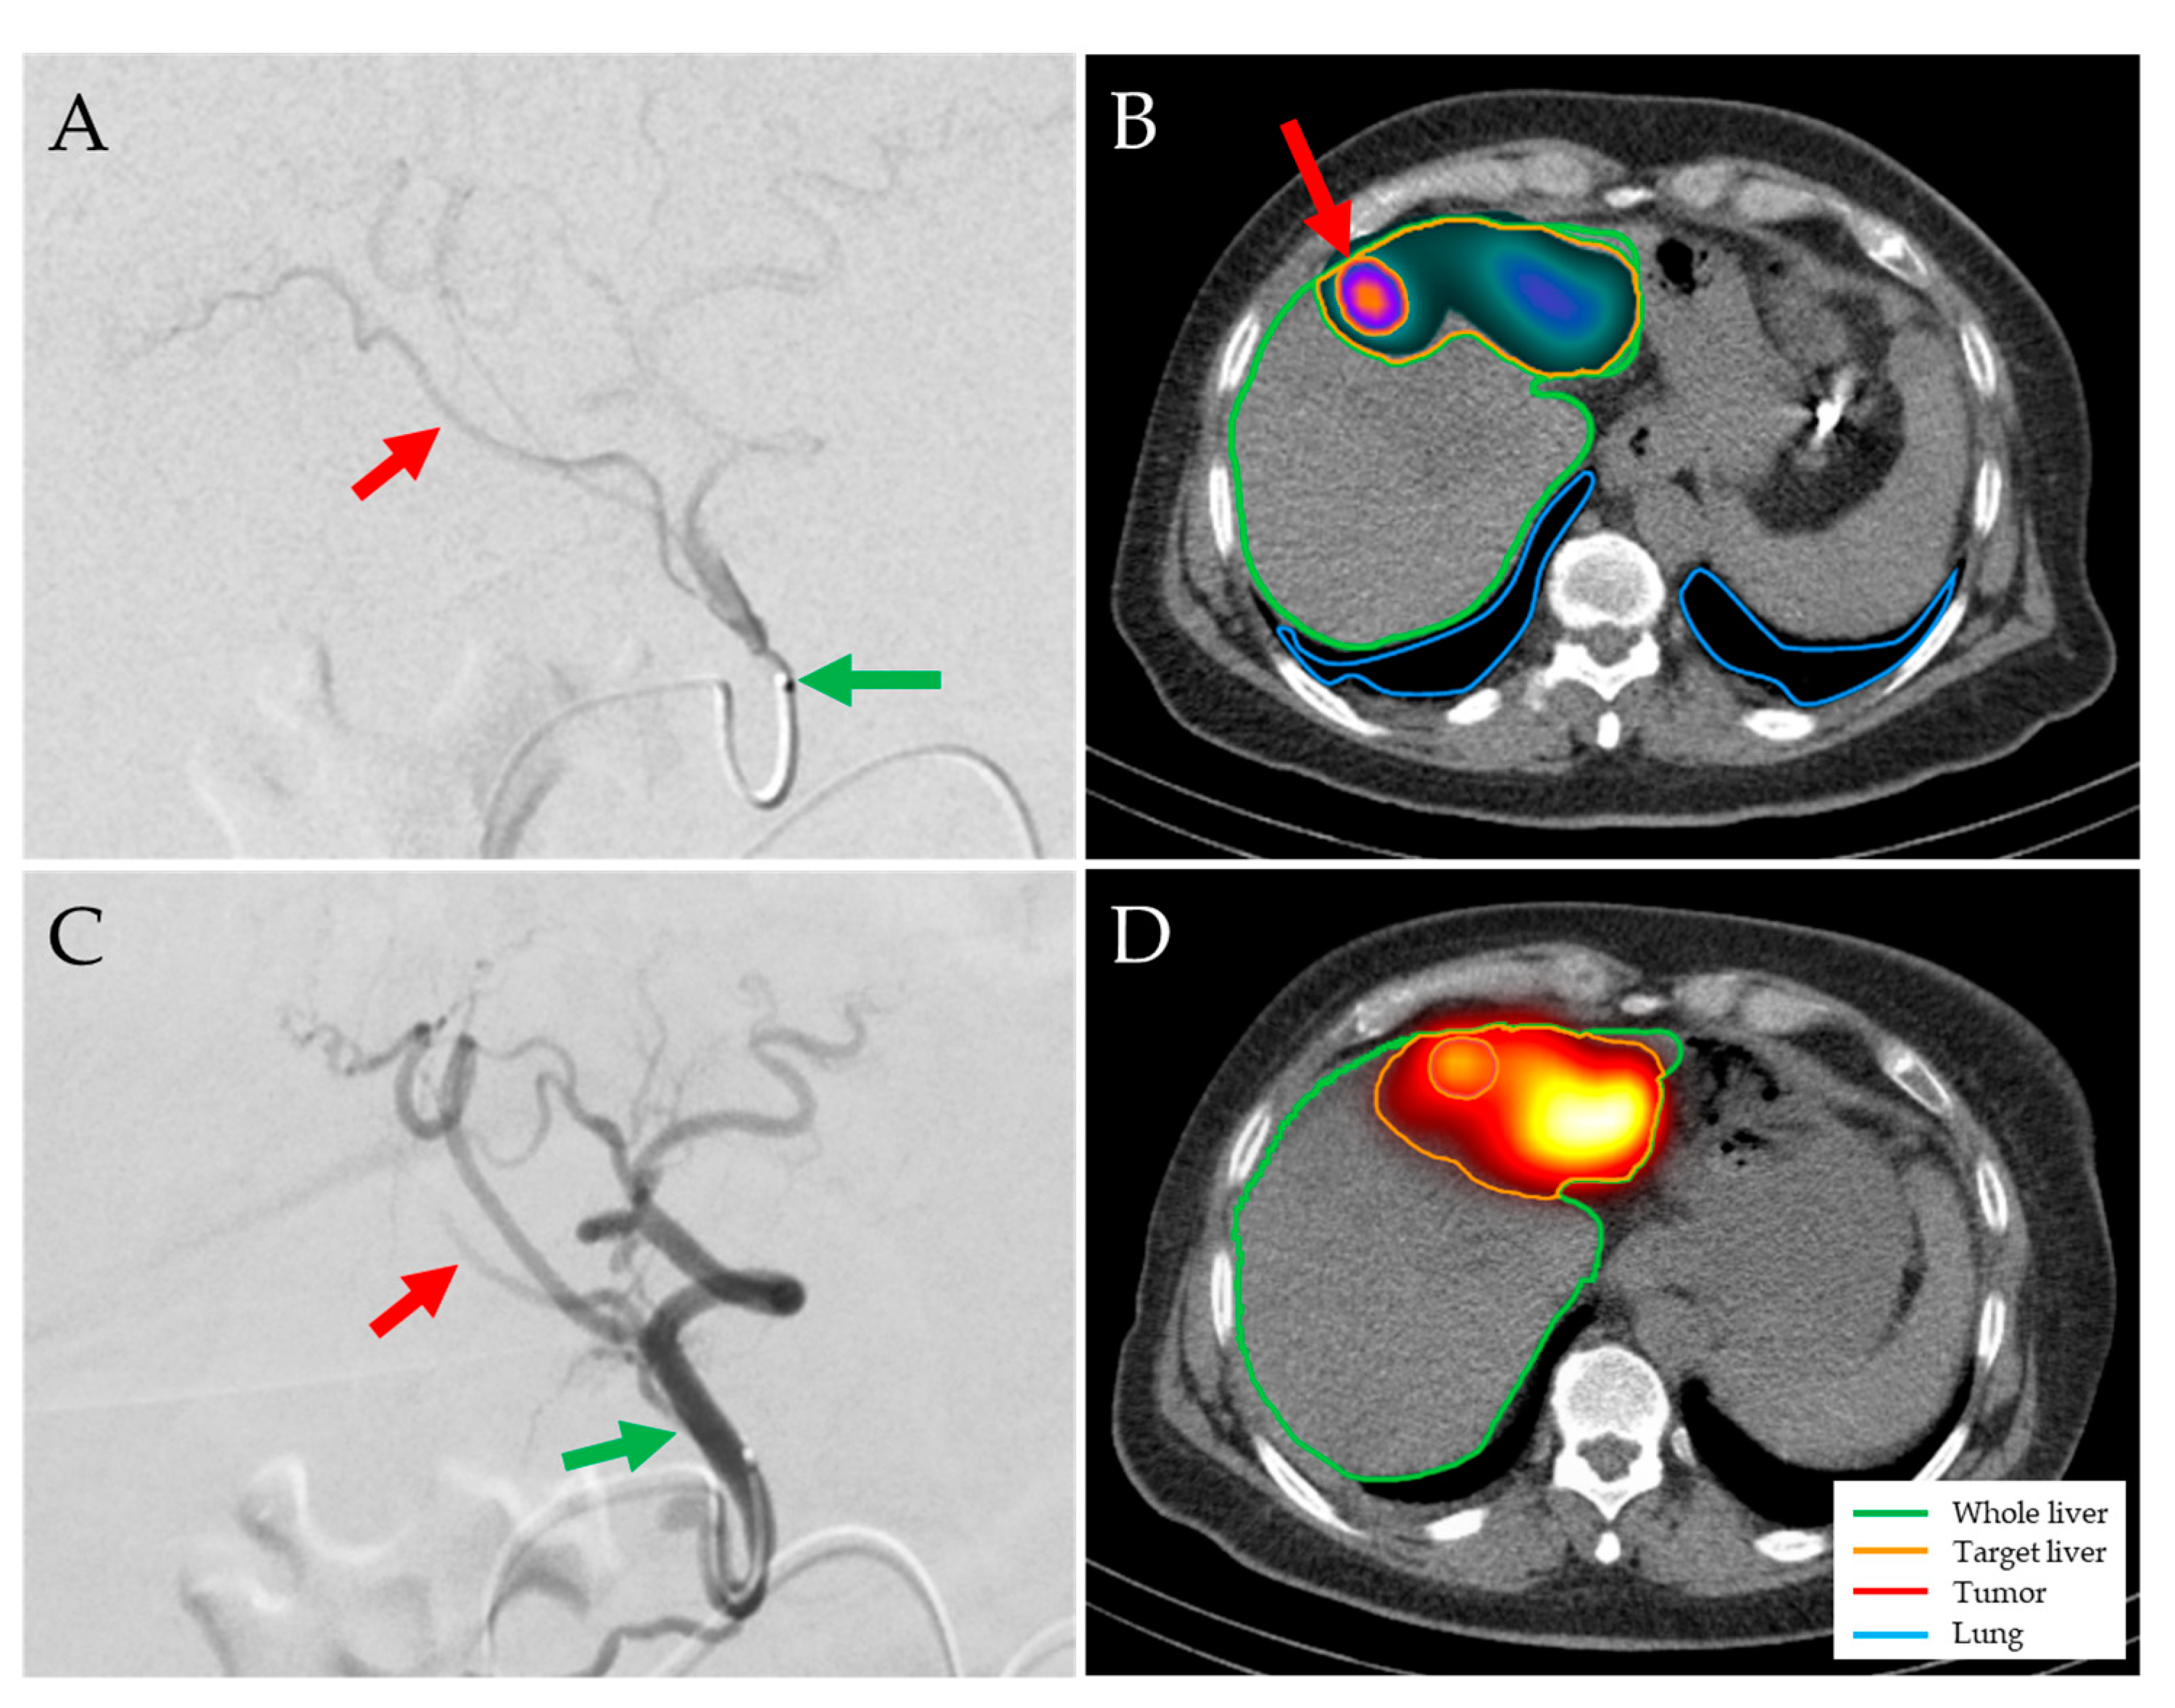

- A 58-year-old man with HCC stage II and severe liver cirrhosis (BCLC D, ALBI grade 3, Child–Pugh score C11, moderate ascites, bridging-to-transplant 166Ho-TARE of liver segment II, target 14% of whole liver, healthy target/tumor doses: 59 Gy/119 Gy). The patient was discharged as planned, but readmitted to hospital with acute or chronic liver failure (ACLF) grade 3, pneumonia, and sepsis. The Child–Pugh score deteriorated to C13. The patient died 6 days after 166Ho-TARE.

- A 74-year-old man with HCC stage II and liver cirrhosis (BCLC B, ALBI grade 2, Child–Pugh score A6, no ascites, palliative 166Ho-TARE of left liver lobe, 43% of whole liver, healthy target/tumor doses: 49 Gy/148 Gy). The follow-up at three months showed PR of the tumor, but moderate ascites (Child–Pugh score B8). The liver function deteriorated rapidly. The patient died 3.2 months after 166Ho-TARE.

- A 69-year-old man with HCC stage IIIB and liver cirrhosis (BCLC B, ALBI grade 2, Child–Pugh score B7, moderate ascites, palliative 166Ho-TARE of right liver lobe, target 55% of whole liver, healthy target/tumor doses: 41 Gy/114 Gy). The follow-up at three months showed PD in both liver lobes with macrovascular involvement and a Child–Pugh score of B8. The patient died 4.0 months after 166Ho-TARE.

- A 65-year-old man with HCC stage II in the liver segment IV, maximum diameter 19 cm compressing the portal vein and liver veins, no liver cirrhosis (BCLC C, ALBI grade 3, Child–Pugh score B8, no ascites, palliative 166Ho-TARE of the liver segment IV, 28% of whole liver, healthy target/tumor doses: 42 Gy/88 Gy; tumor not completely perfused). The follow-up at three months showed PR of the tumor and tumor progression in adjacent liver segments. Four months after 166Ho-TARE, the liver function deteriorated rapidly (Child–Pugh score C13). The patient died 5.6 months after 166Ho-TARE.